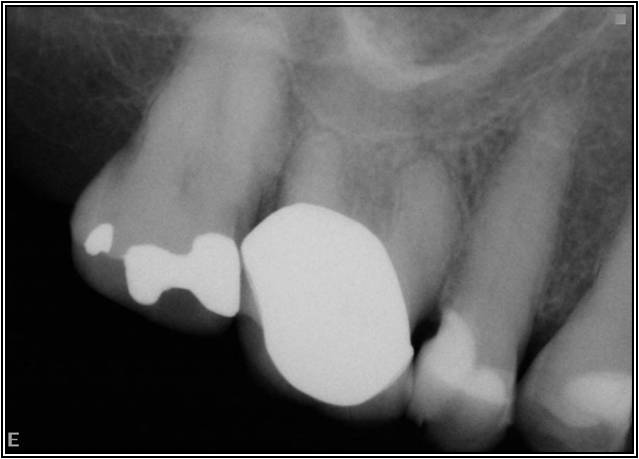

Figure 4 through Figure 10 depict several teeth that have conservative accesses while still allowing the clinician to adequately instrument and clean each tooth to achieve effective root canal therapy. The success of these cases still hinges on the proper cleaning and shaping of the root canal system, and while conservative accesses are desirable, too small of an access can lead to missed canals, poor instrumentation, improper cleaning, and, ultimately, a failed procedure.

The question remains: how often should clinicians use apex locators, and are they really necessary? Because studies have shown them to be up to 96% accurate,8 it stands to reason that they could be used in every case possible. In some instances, the apex cannot even be seen radiographically. In these cases, using an apex locator is imperative to finding the true working length of the canals. The question remains: how often should clinicians use apex locators, and are they really necessary? Because studies have shown them to be up to 96% accurate,8 it stands to reason that they could be used in every case possible. In some instances, the apex cannot even be seen radiographically. In these cases, using an apex locator is imperative to finding the true working length of the canals. Figure 10 and Figure 11 through Figure 14 demonstrate two such cases; they likely would not have been successfully completed without the use of an apex locator. Even the final PA (Figure 14) does not clearly depict where the canals end.

Working films or radiographs, however, should not be completely eliminated from the clinician’s armamentarium. While practitioners may legally only be required to depict a preoperative and postoperative radiograph, from an endodontic point of view at least one working radiograph should always be taken. This does not mean that a master file radiograph has to be taken; however, it is prudent to take one in cases in which the anatomy is challenging, and the author recommends always taking a master cone radiograph (Figure 11 through Figure 14).

The master cone PA is the last indicator clinicians have in assessing whether or not their working lengths were truly accurate. This radiograph is crucial in affording the practitioner the opportunity to make adjustments to properly complete the procedure to the desirable lengths. An example is presented in Figure 15 through Figure 18. Figure 16 and Figure 17 show a master cone PA that demonstrates two of four canals to proper length. After adjusting the length of the other two master cones, the clinician was able to correct the lengths to produce a more appropriate result, as seen in Figure 18.